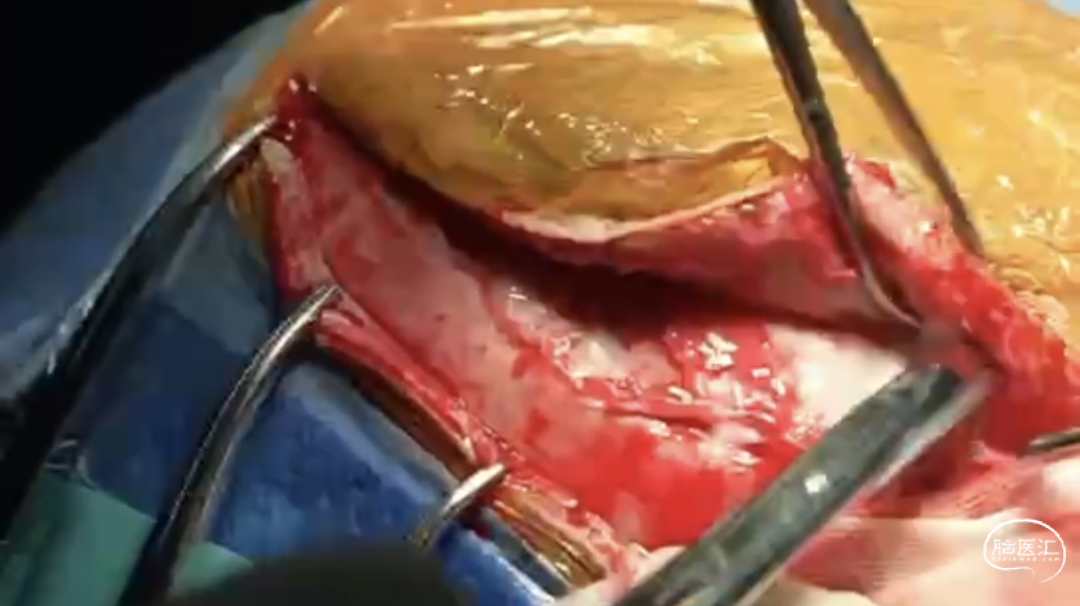

步骤一:分离头皮、帽状腱膜、游离骨膜,清除骨窗边上的软组织,暴露骨窗

步骤二:分离颞肌,颞肌分离完毕后把颞肌翻开,充分暴露骨窗